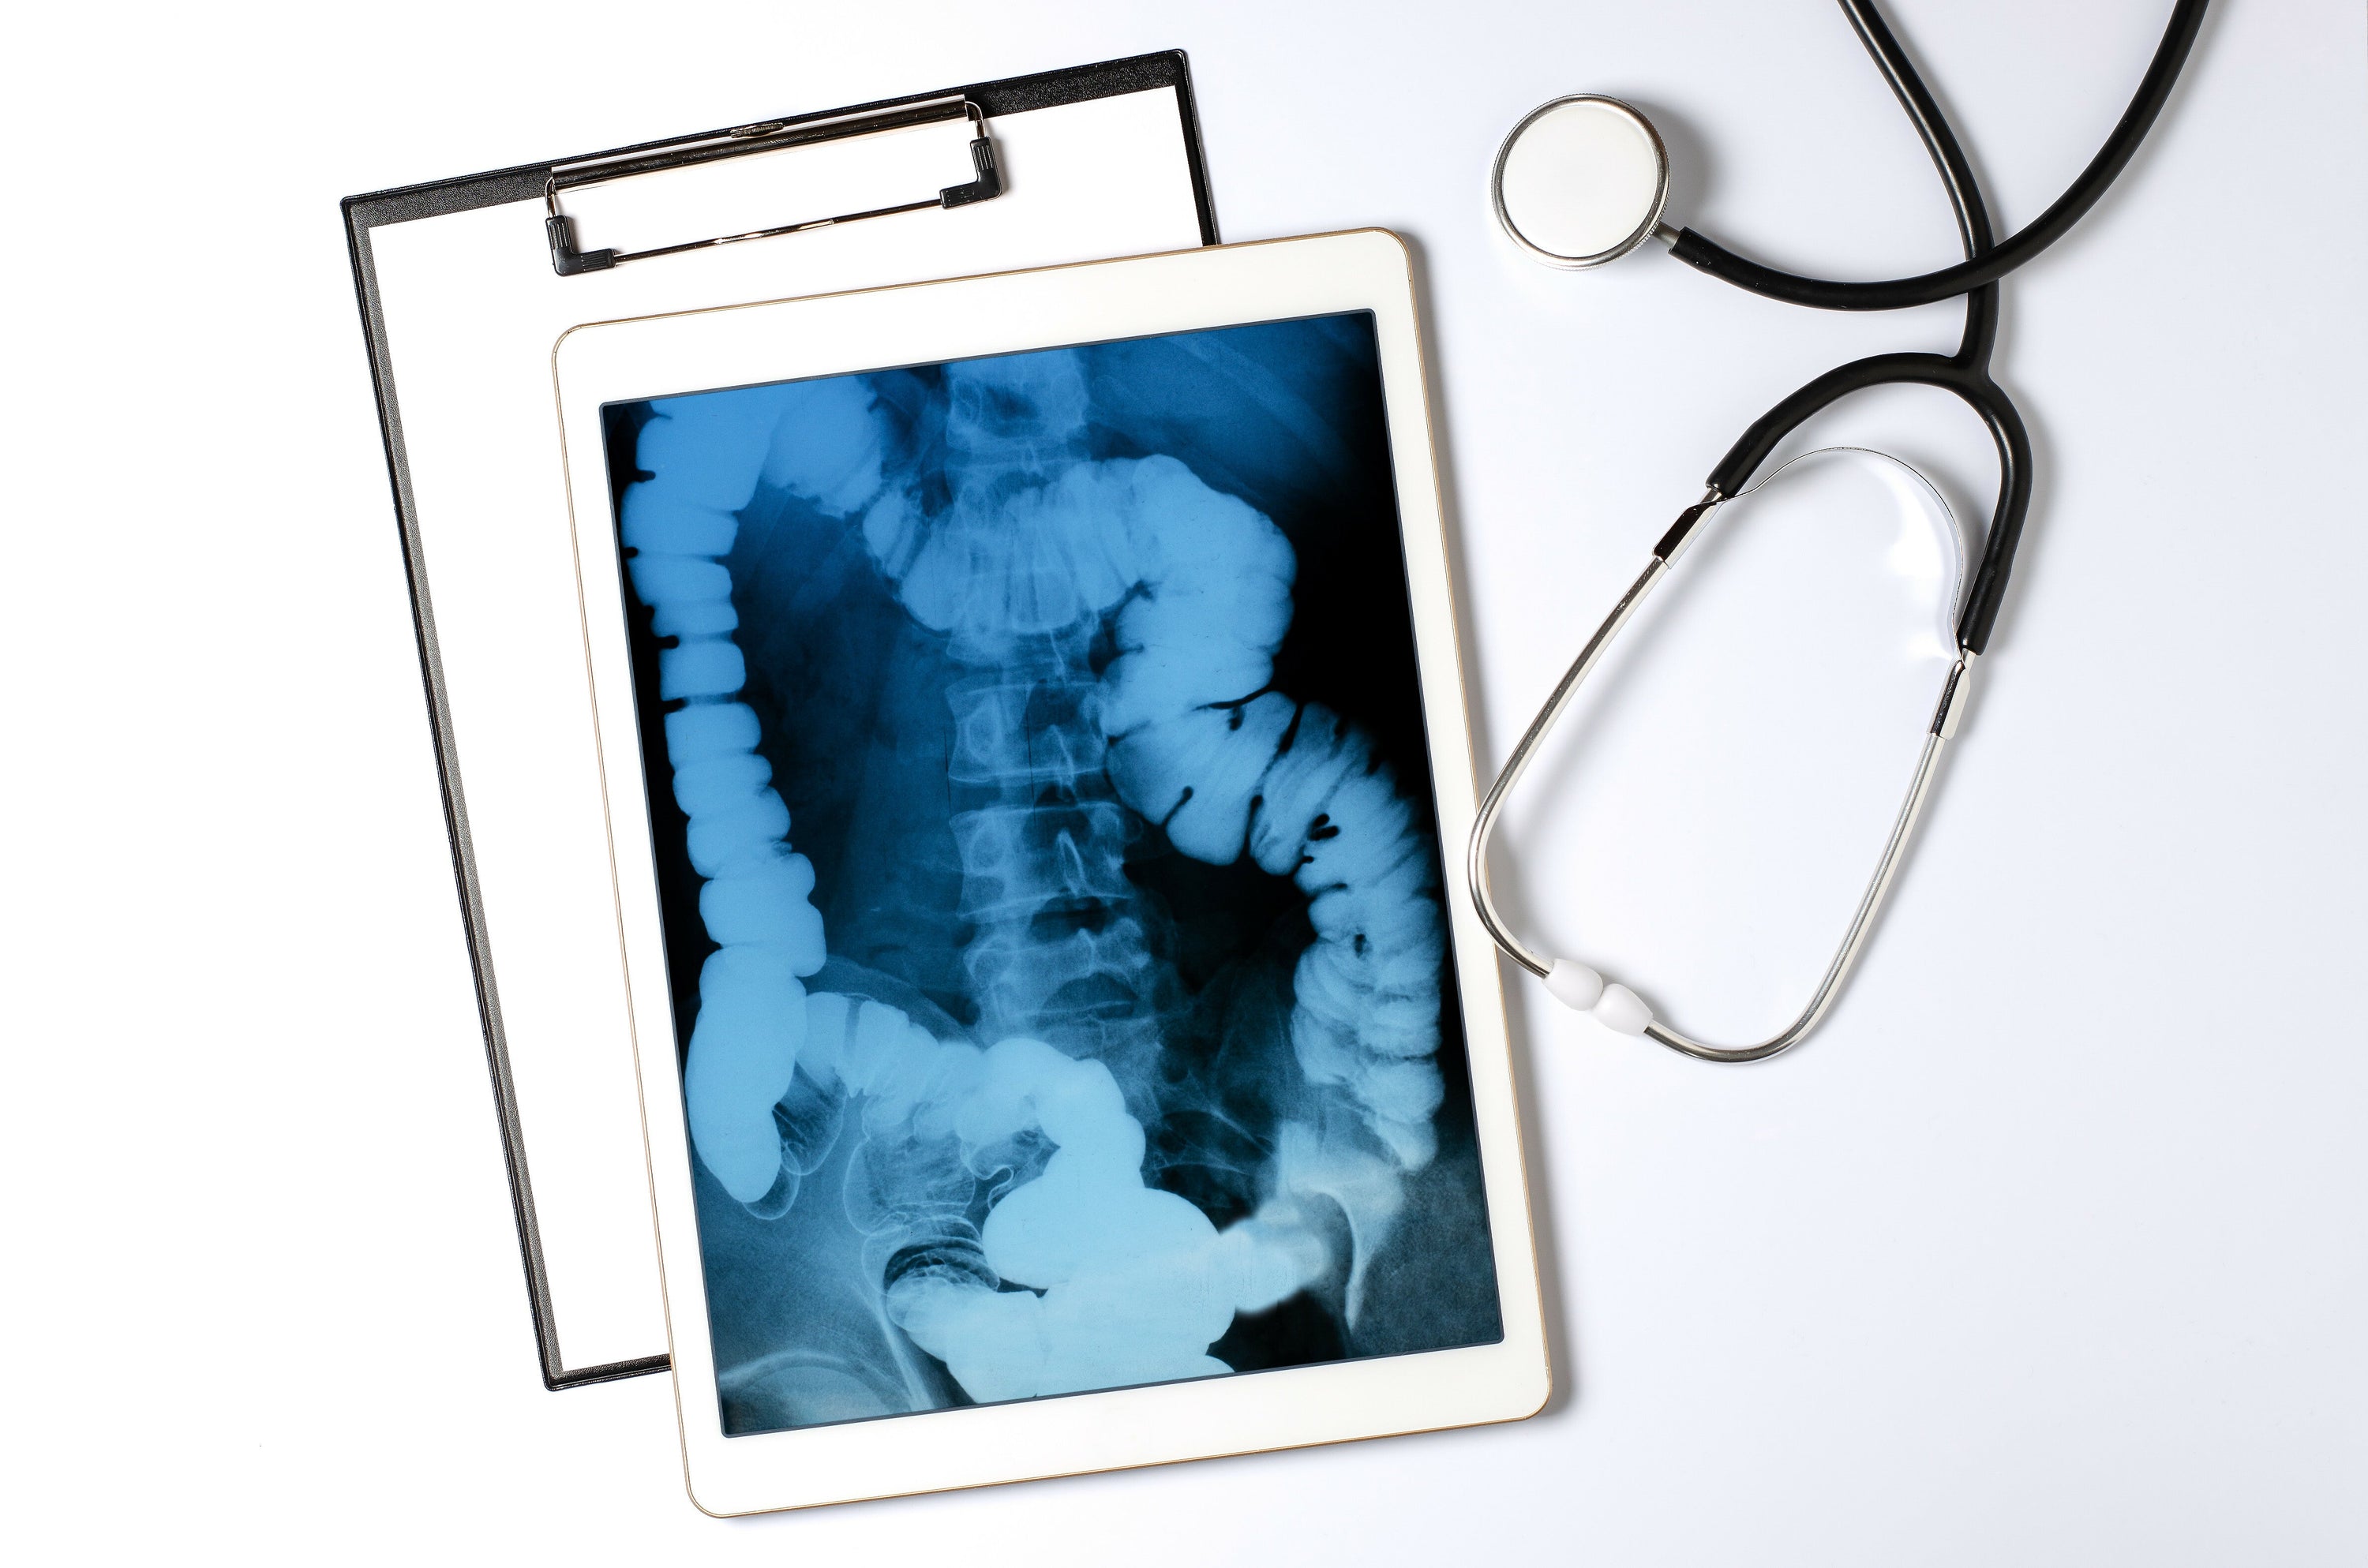

Die Funktion eines Röntgengeräts ist eine Abbildung von etwas, das unterhalb einer undurchsichtigen Oberfläche liegt. Bei einem klassischen Röntgengerät in der Medizin handelt es sich im Wesentlichen um eine Röhre, die Elektronen auf ein Metallstück schießt. Beim Aufprall der Elektronen entstehen dann Röntgenstrahlen, die durch den zu untersuchenden Körper geleitet werden. Da verschiedene Materialien die Strahlen unterschiedlich absorbieren, entsteht ein Bild auf einem sogenannten Detektor oder einer Fotoplatte. Dabei werden die Knochen in Weiß, weiches Gewebe in Grautönen und die Luft schwarz abgebildet. Heutzutage sind digitale Röntgentechniken in der Lage, diese Strahlen direkt in Bilder umzuwandeln, die auf einem Bildschirm angezeigt werden. Diese Modernisierung ermöglicht was eine sofortige Beurteilung der Bildgebung durch den Mediziner.

Erstaunlich an Röntgenbildern ist, wie sie die verborgenen Strukturen unseres Körpers offenbaren. Sie ermöglichen es Ärzten, Knochenbrüche zu diagnostizieren, Fremdkörper zu lokalisieren oder die Gesundheit von Gelenken zu beurteilen. Röntgenaufnahmen sind dabei nicht nur auf den menschlichen Körper beschränkt. Auch Einblicke in die Anatomie von Tieren sind mit der Röntgen-Technik möglich, was für veterinärmedizinische Diagnosen unerlässlich ist. Röntgen-Bildgebungen sind nicht nur für medizinisches Fachpersonal von Interesse, sondern faszinieren auch die Allgemeinheit, da sie etwas sichtbar macht, was für das bloße Auge nicht erkennbar ist.